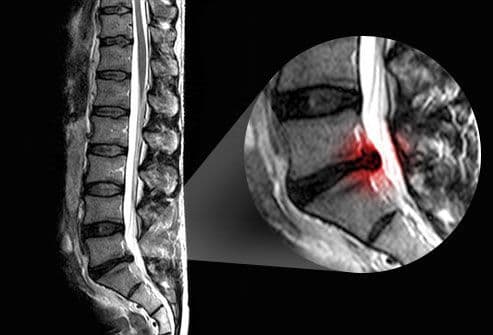

या विकाराचं निदान करण्यासाठी डॉक्टर सगळ्यात आधी प्रत्यक्ष शारीरिक चाचणी म्हणजे फिजिकल एक्झाम करतात. यात पाय गुडघ्यात न वाकवता वर उचलणं, टाचेवर किंवा चवड्यांवर चालणं अशा क्रिया रुग्णाला करायला सांगितल्या जातात. या चाचण्यांमधून सायटीक नर्व्हमध्ये काही समस्या आहे का याचा अंदाज येतो. त्यानंतर एक्सरे, सीटी स्कॅन, एमआरआय या माध्यमांतून प्रत्यक्ष रोगनिदान करता येतं.